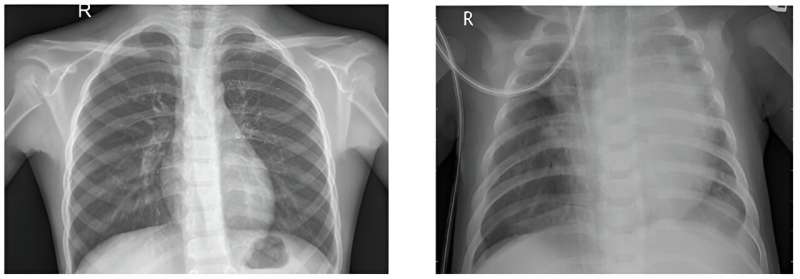

肺炎是一种导致呼吸困难的肺部感染,最常见的诊断方法是通过胸部x光检查。通常,这些胸部x光片是由放射科医生阅读的,但劳动力短缺意味着,在未来,可能更难及时得到诊断。

他说:“机器学习用于预测,在医疗保健领域,我们希望预测某人是否患有疾病。”“如果你给出足够多的肺炎和非肺炎的图像例子,因为有两种情况,这被称为二元分类。”